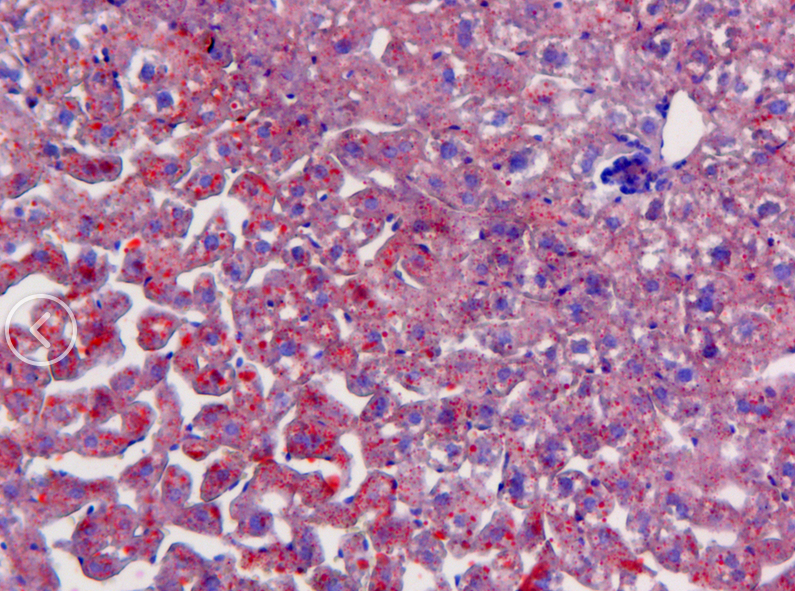

油紅O脂肪染色法是指在日常病理診斷和科研工作中為了顯示組織內(nèi)的脂肪常采用油紅O進(jìn)行染色的方法,油紅O為脂溶性染料,在脂肪內(nèi)能高度溶解,可特異性的使組織內(nèi)甘油三酯等中性脂肪著色。

【技術(shù)原理】

油紅O染色液主要用于顯示組織器官的脂肪變性和類脂質(zhì)的異常沉著,常發(fā)生于肝、腎、心等實(shí)質(zhì)臟器的脂肪變性,細(xì)胞內(nèi)出現(xiàn)多數(shù)中性脂肪滴;鑒別和診斷脂肪組織中所發(fā)生的腫瘤及其性質(zhì)。標(biāo)本不采用含有乙醇的固定液(如需要固定可采用 10%的福爾馬林)、也不采用石蠟切片,需用冰凍切片或碳蠟切片。脂肪的陽性染色結(jié)果呈橘黃至紅色,但具體顏色因脂質(zhì)濃度而定。

優(yōu)秀案例展示

中性脂肪 橙紅色或橘紅色

細(xì)胞核 藍(lán)色